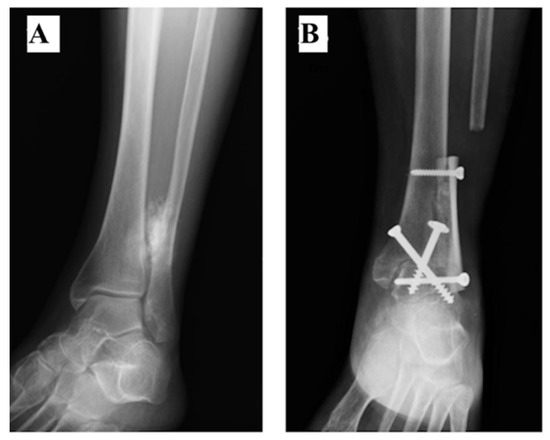

| 1 | 133 | 7.5 | No | Yes | Yes | No | 0 | TTA | 3 | - | No | 27 |